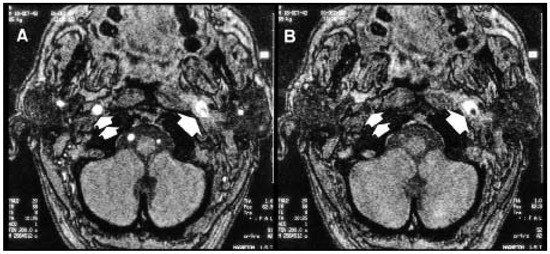

Seltene Ursache Multipler Ipsilateraler Hirnnervenausfälle

by S. Rüegga, S. Wetzelb and A. J. Stecka

Swiss Arch. Neurol. Psychiatry Psychother. 1999, 150(6), 283-286; https://doi.org/10.4414/sanp.1999.01122 - 1 Jan 1999

Viewed by 32

Abstract

We report on a patient with subacute infranuclear palsies of lower cranial nerves IX–XII (Collet- Sicard-syndrome) as a result of spontaneous periadventitial dissection of the ipsilateral inner carotid artery. Emphasis is given on probable pathomechanisms and different etiologies of this syndrome. Additionally, a [...] Read more.

We report on a patient with subacute infranuclear palsies of lower cranial nerves IX–XII (Collet- Sicard-syndrome) as a result of spontaneous periadventitial dissection of the ipsilateral inner carotid artery. Emphasis is given on probable pathomechanisms and different etiologies of this syndrome. Additionally, a short summary concerning epidemiology, clinical presentation and therapeutic issues of dissection of the inner carotid artery is presented. Full article

Show Figures

Figure 1